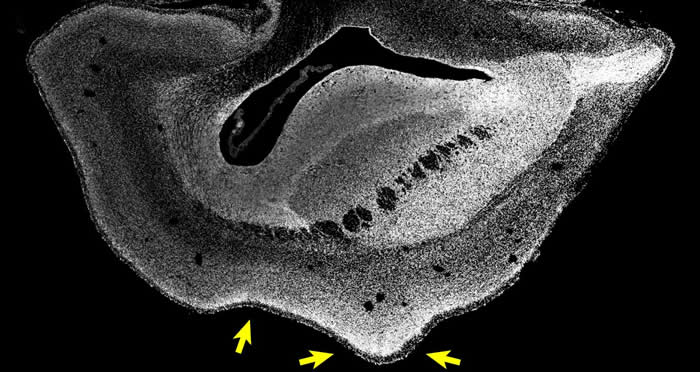

101日龄普通狨猴胎儿的大脑切片(Credit : Heide et al. / MPI-CBG)

(蜘蛛网eeook.com报道)ARHGAP11B是一种人类特有的基因,过去的研究认为它可能与大脑发育有关。近日,在《科学》发表的一项研究中,研究人员将ARHGAP11B基因转入普通狨猴胚胎内。结果显示,101日龄(正常出生时间前50天)的普通狨猴胎儿大脑的新皮质变大,且大脑表面折叠增加,其皮质板也发育得更厚。此外,研究还发现,一些在灵长类演化过程中数量增加的神经元类型,在这种转基因胎儿的大脑内也有所增加。这一研究证明,人类特有的基因ARHGAP11B的充分表达,会导致灵长类大脑变大,从而说明这一基因在人类大脑的演化过程中,起到了重要的作用。